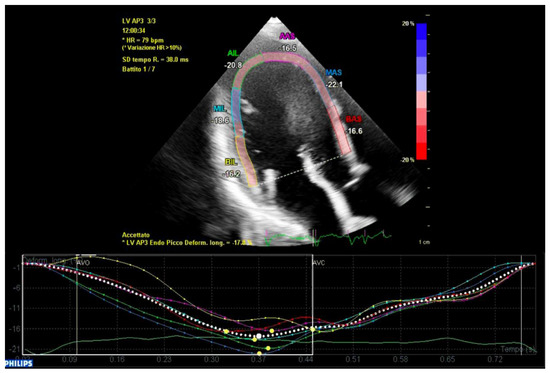

When it was analyzed by single segments (basal, middle and apical), the mechanical dispersion of the apical segments did not differ between the two groups, while the basal and middle segments showed each an increased mechanical dispersion in the ICD-MVP group that did not reach statistical significance when it was analyzed alone (basal or middle), but it was statistically significant when it was analyzed in a combined way (ICD-MVP: 117 ± 31 ms, A-MVP: 76 ± 48 ms; p = 0.03).

In conclusion, the variables that were identified as the predictors of major arrhythmic events with the highest AUC (>0.80) within our high-risk population of arrhythmic MVP patients were the AML length (measured as shown in Figure 7), the S3 of the inferolateral basal segment and the mechanical dispersion of the basal and mid-ventricular segments calculated with speckle tracking analysis (Figure 8 and Figure 9).

Figure 8. Mechanical dispersion in a patient from the ICD-MVP group. The segments that present greater peak systolic shortening time dispersion are the anterior-septal basal segment (in red) and the inferolateral basal segment (in yellow). Apical segments present a synchronous peak systolic shortening.